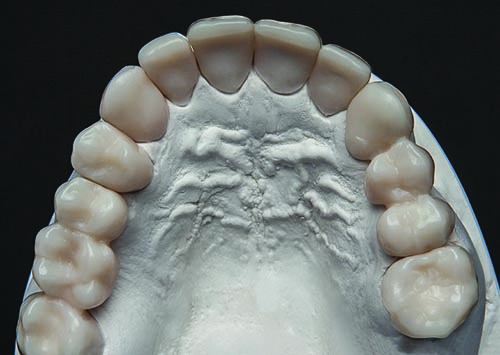

Fig. 11: Preoperative models were mounted, studied and used to determine ratios that should be incorporated into the restoration designs.

Figs. 16–19. In anticipation of the second appointment two weeks later, the study models were prepared for long-term provisional restorations and scanned with a 3Shape scanner. This enabled the provisional restorations to be designed digitally and then milled chairside from composite blocks (e.g., Telio CAD, Ivoclar Vivadent). In particular, during the second appointment, posts and cores would be placed in teeth #6 through #8, #22 and #28, and initial tooth preparation and long-term provisional installation would be performed for teeth #2 through #14.